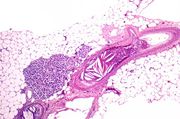

| 21:42, 20 August 2013 | IPLab6MM2.jpg (file) | 81 KB | This higher-power photomicrograph shows the junction between an amorphous hyaline-appearing area (amyloid) on the right and cellular areas (plasmacytoid cells) on the left. | 1 | |